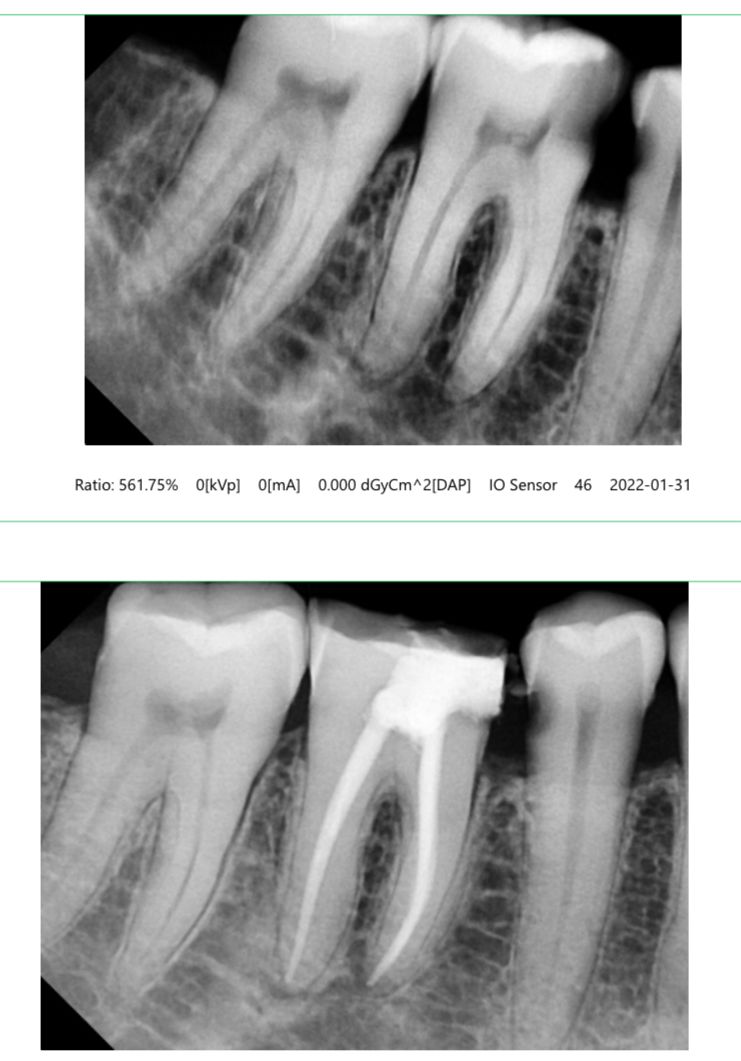

Diagnosis & X-ray – To identify the infected area.

Cleaning the Canals – Removal of infected pulp and bacteria.

Shaping & Disinfection – Preparing the canals for filling.

Filling the Canal – Sealing with biocompatible materials.

Crown Placement – Recommended for added protection and strength.

High-end digital X-rays and rotary endodontics